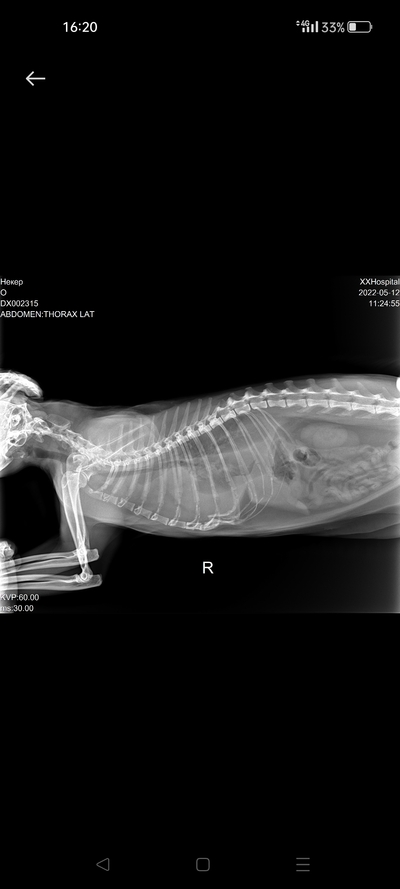

Клиника отдала мне оригиналы снимков, у них снимки только умеет делать рентген. Залил фото снимков на гугл.диск:

15 декабря примерно:

https://drive.google.com/file/d/1xLXBgF-A9EkaQEcYnz70CIhmz3-...

https://drive.google.com/file/d/1XtUZ_A5pP6sWWCSJjFr9AXJkzPA...

конец января:

https://drive.google.com/file/d/1PBm-ZrvmQlNTYObeOk4UMaEPZc9...

Пришлось заходить с компьютера, что бы хорошо посмотреть снимки. Скорее всего трещину перепутали с зоной роста (отметил желтым). Наличие зон роста - это не проблема. По рентгену определяются участки костей с явным признаком воспалительного процесса (паностеит, отметил фиолетовым), рекомендовал бы рентгенографическое исследование контрлатеральной конечности, так же есть снижение кортикального слоя (отметил красным), стоит поискать проблемы в питании (возможно, с натуральной еды, перейти на некоторое время на коммерческие корма). Плюс, что бы меньше болело, назначаются противовоспалительные препараты на длительное время